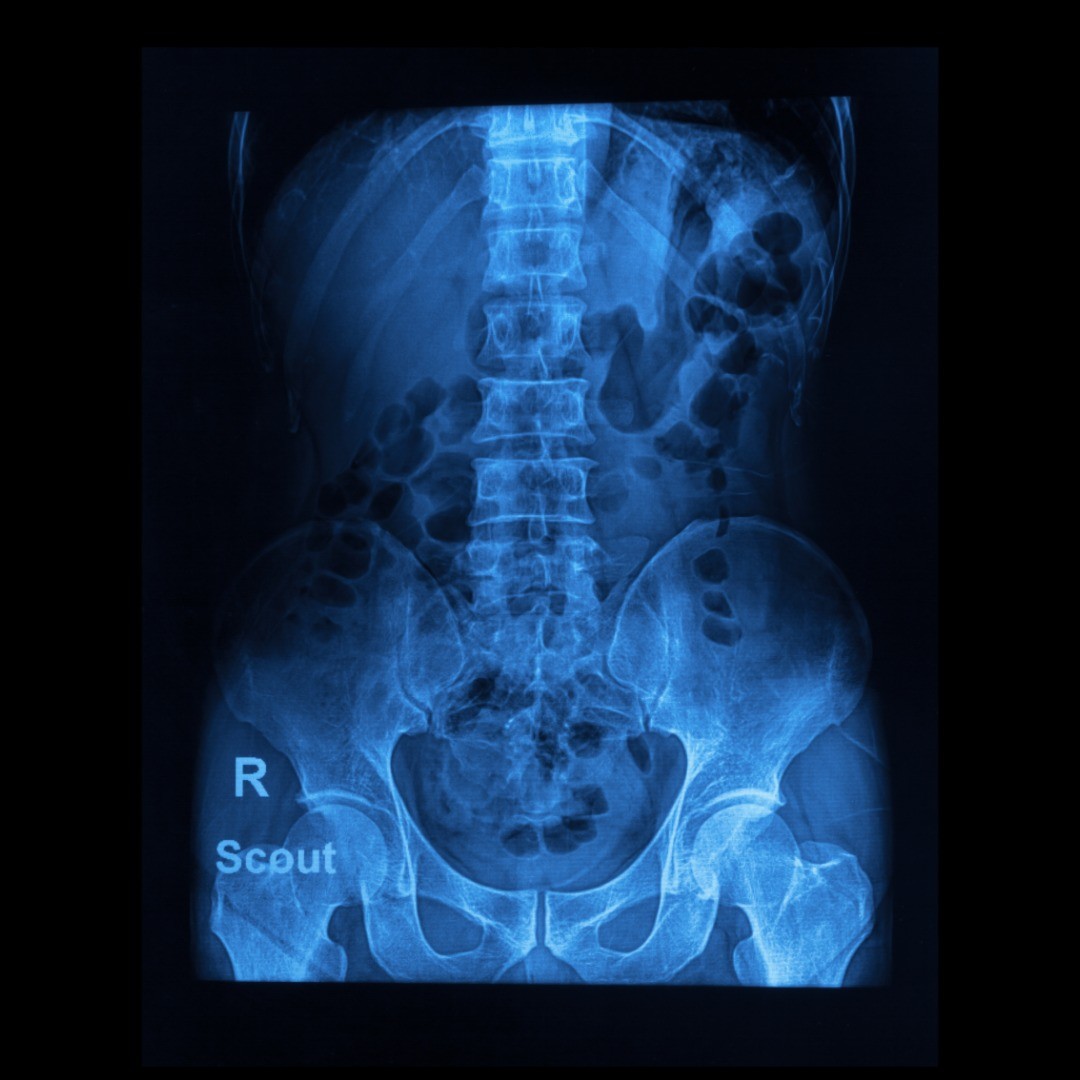

Each candidate is carefully evaluated to ensure that the chronic pain and debilitating symptoms are not from another untreated condition such as a herniated disc, nerve compression or arthritis. Kyphoplasty is recommended after more conservative treatments such as bed rest, medication and physical therapy have been tried with negligible results.

The multi-disciplinary team of specialists at NSPC Brain & Spine Surgery (NSPC) (NSPC) will work together to determine whether kyphoplasty is the best treatment option for your chronic and debilitating back pain caused by a spinal fracture. Our experienced team of professionals will review your medical history, give you a physical exam and examine your blood work.

For the kyphoplasty procedure, the patient will need to lie face down for one to two hours during the procedure, usually under general anesthesia.